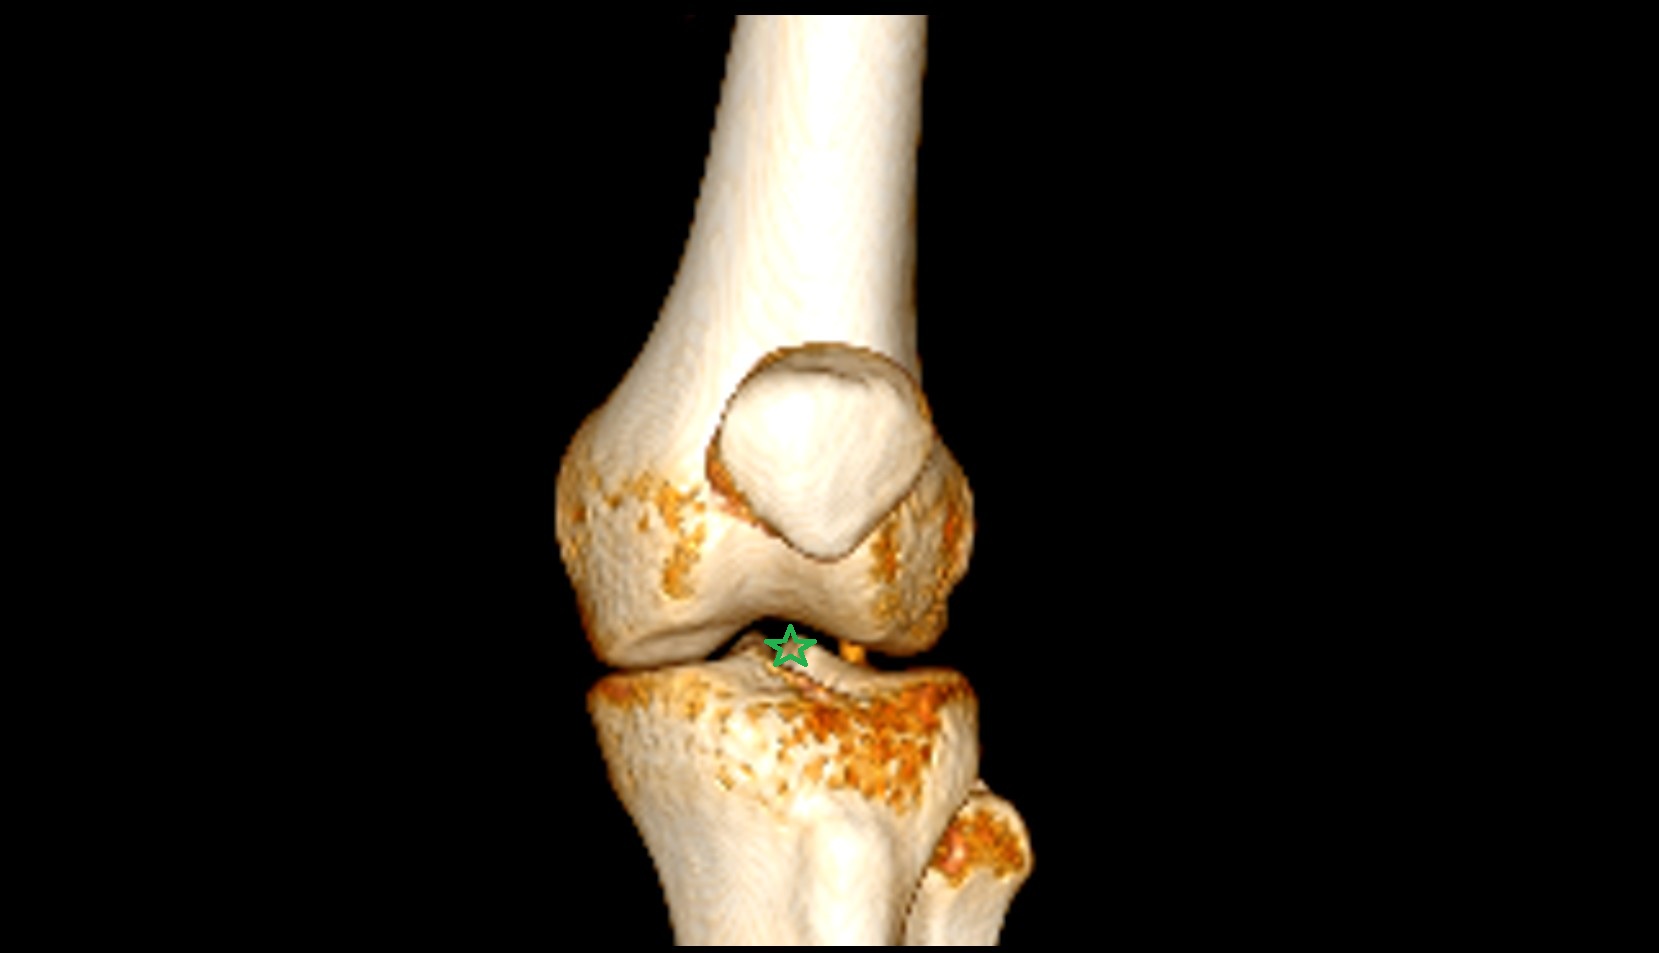

- Knee Joint

- Lateral condyle of femur

- Medial condyle of femur

- Femoral condyle articular cartilage

- Tibial condyle articular cartilage

- Medial tibial plateau

- Lateral tibial plateau